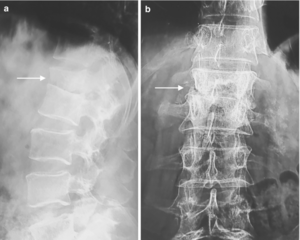

X-Ray

Spine Tuberculosis Diagnosis | Dr. Sudheer Pothu

Patients with relevant symptoms and risk factors should be suspected of having spine tuberculosis. To confirm the diagnosis, the following tests ar...